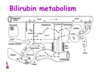

Bilirubin Metabolism

- we have a regular turnover of RBC’s (110 days) and we want to conserve ironand conserve Hb –>happening in spleen

- bilirubin is not solube in water- trafficked using albumin

- conjugated in the hepatocyte –> makes it water soluble (can then float in fluid without carrier)

- conjugated bilrubin will be converted urobilin or stercobilin or can be excreted in the urine

Bilirubin

Bilirubinemia- Hemolysis

- if you have excess break down of RBC’s

- the hepatocytes can only conjugate so much

- the key limiting step though is the EXCRETION INTO THE BILE

- there will be back up into the system, you will start to leak out the conjugated bilirubin which is soluble and you will see it being released in urine